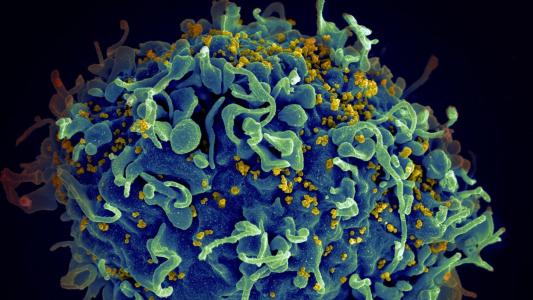

At long last, we might have an HIV vaccine

Due to HIV-1's extraordinary diversity, a vaccine needs to induce antibodies that can target many different strains.